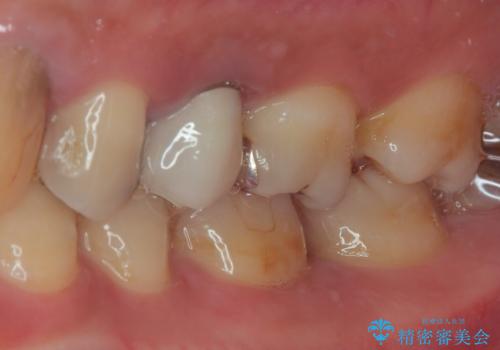

機能面、見た目共に満足していただきました。今後はメンテナンスで通っていただく予定です。

- かみ合わせや歯ぎしりが強すぎる方はセラミックが割れてしまう可能性があります